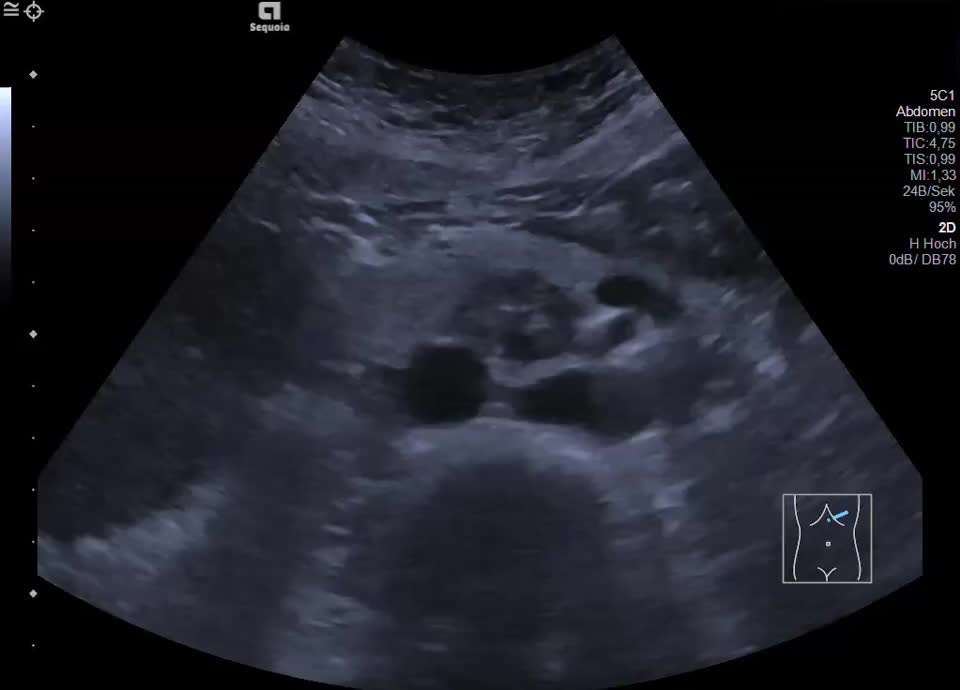

Case

60-year-old female patient with incidental finding of serous cystadenoma one year ago. Current follow-up examination reveals small cystic mass (honeycomb pattern visible on EUS) of constant size in the head of the pancreas/uncinate process. In the transcutaneous B-scan, central echogenic portion (central scar), hypervascularized on color Doppler sonography.